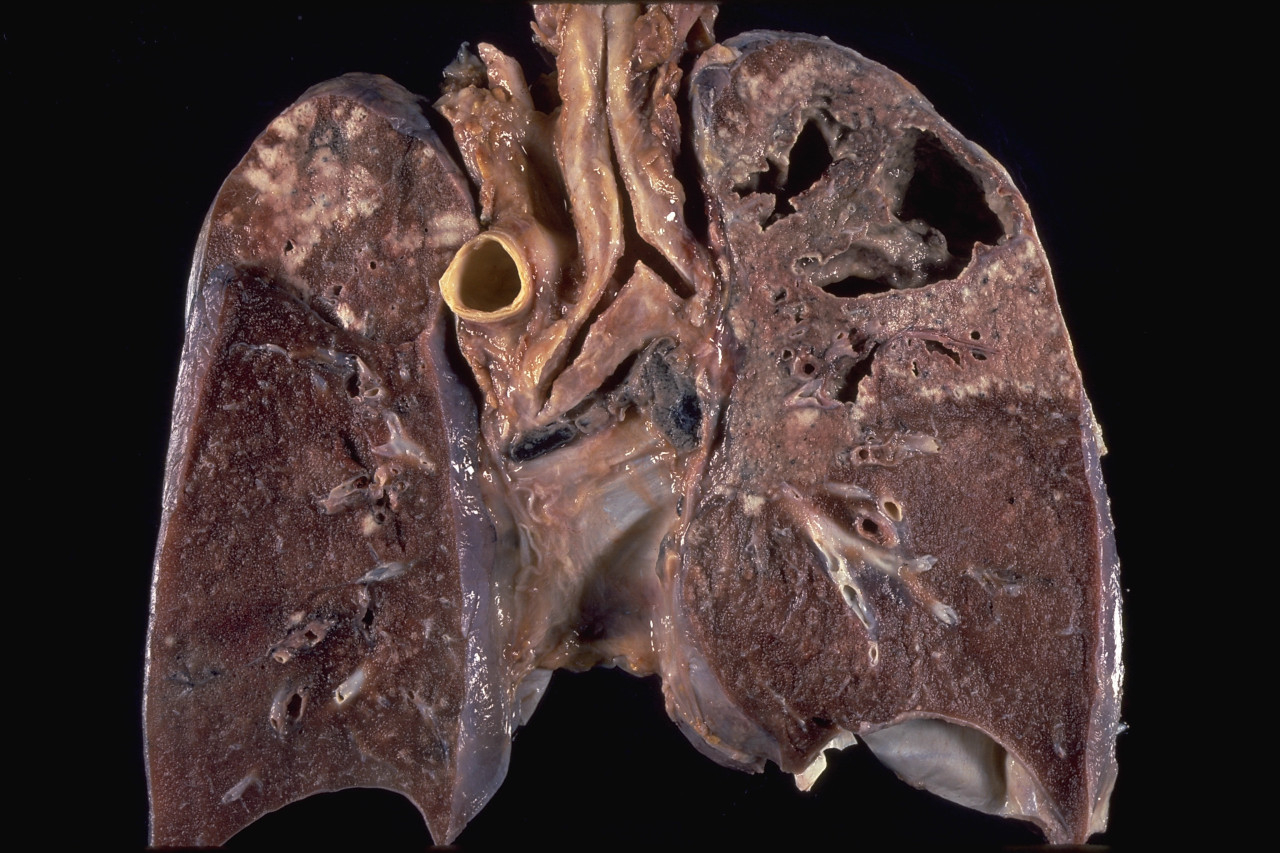

In contrast, the 35 patients who received streptomycin and potassium iodide showed considerable improvement over the course of 60 days. The improvements were noted on both chest x-ray and in changes in weight. The scientists noted that patients experience no negative side effects when given potassium iodide with streptomycin as an alternative treatment for tuberculosis. Pleural cavity changes were significant in this group with the small cavities in the lungs of five of the patients closing completely. The scientists noted that patients receiving potassium iodide and streptomycin didn’t always need surgical collapse therapy and far-advanced and inoperable cases of tuberculosis could be successfully treated in a manner that would allow for surgical intervention.